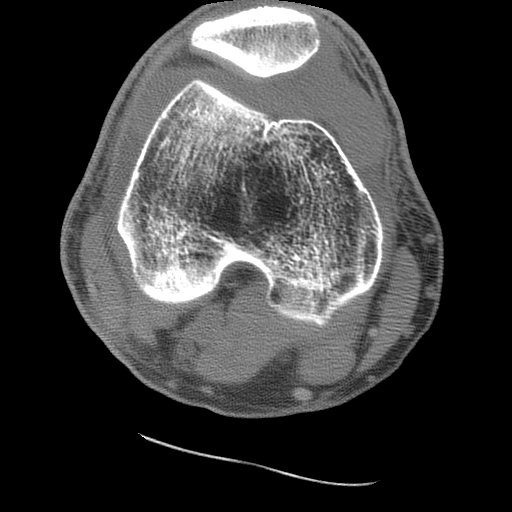

CASE 1: These two CT images are from the 50 year old male who fell one day prior to presentation. His radiographs and MRI may be viewed as well.

Image 1: Axial CT of the knee (soft tissue window) shows the comminuted fracture of the posterior aspect of the tibial plateau. CLICK TO ENLARGE.